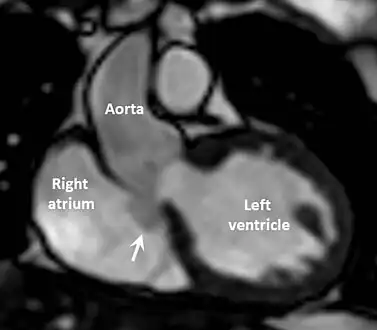

Cardiac MRI scan showing intact sinus of Valsalva aneurysm (arrowed) extending from non-coronary cusp to right atrium.